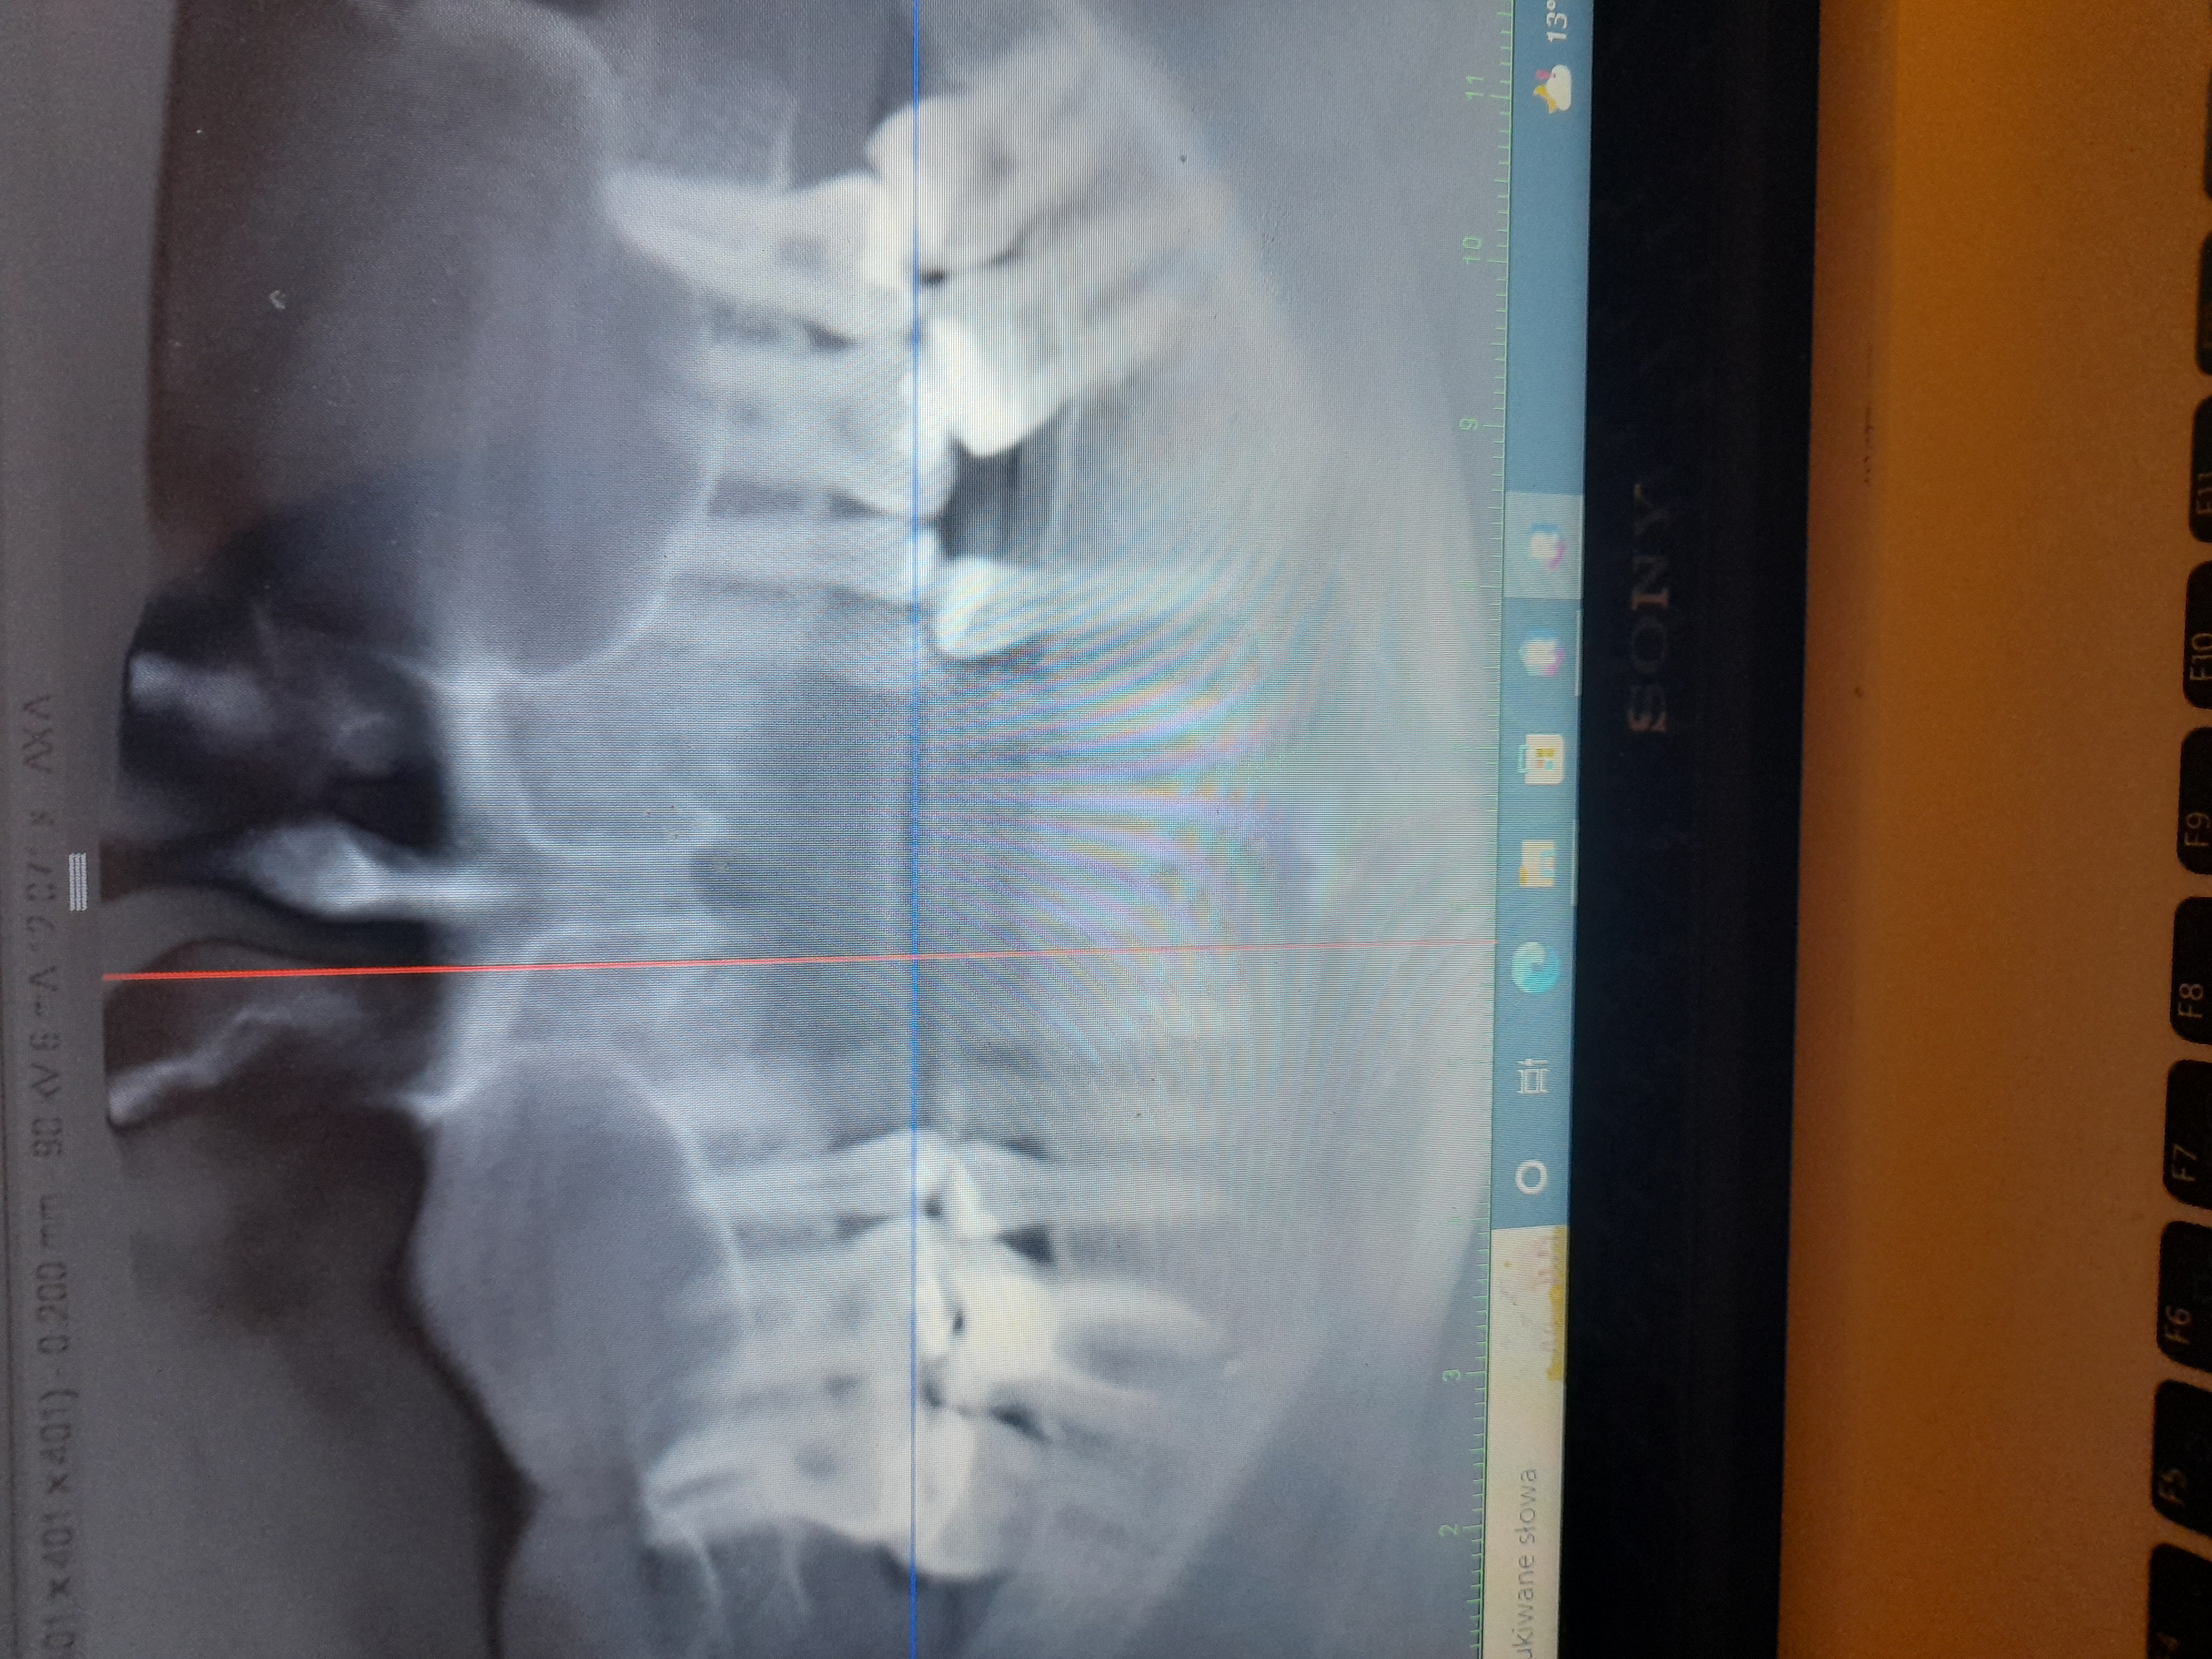

Polipowate zgrubienie śluzówki całej lewej zatoki szczękowej

1 kwietnia wydzlo mi polipowate zgrubienie slozowki calej lewej zatoki szczekowej a w prawej w zachylku zebodolowym 15 mm. Jeden mi powoedzial lekarz ze to wydzielina. Bralam sterydy dwa miesiace i nadal to samo. Boje sie ze jak mam.cala taka lewa zatoke zawalona jakimis zmianami i jakby plynem bo ci lekarze a bylam u kilku nie wiedza czy czasem tam plynu nie ma to wreszcie dostane sepsyalbo czegos gorszego raka lub ze te zmiany zniszcA mi kosci w zatoce. Wysylam zdjecie. Ktos pomoze?